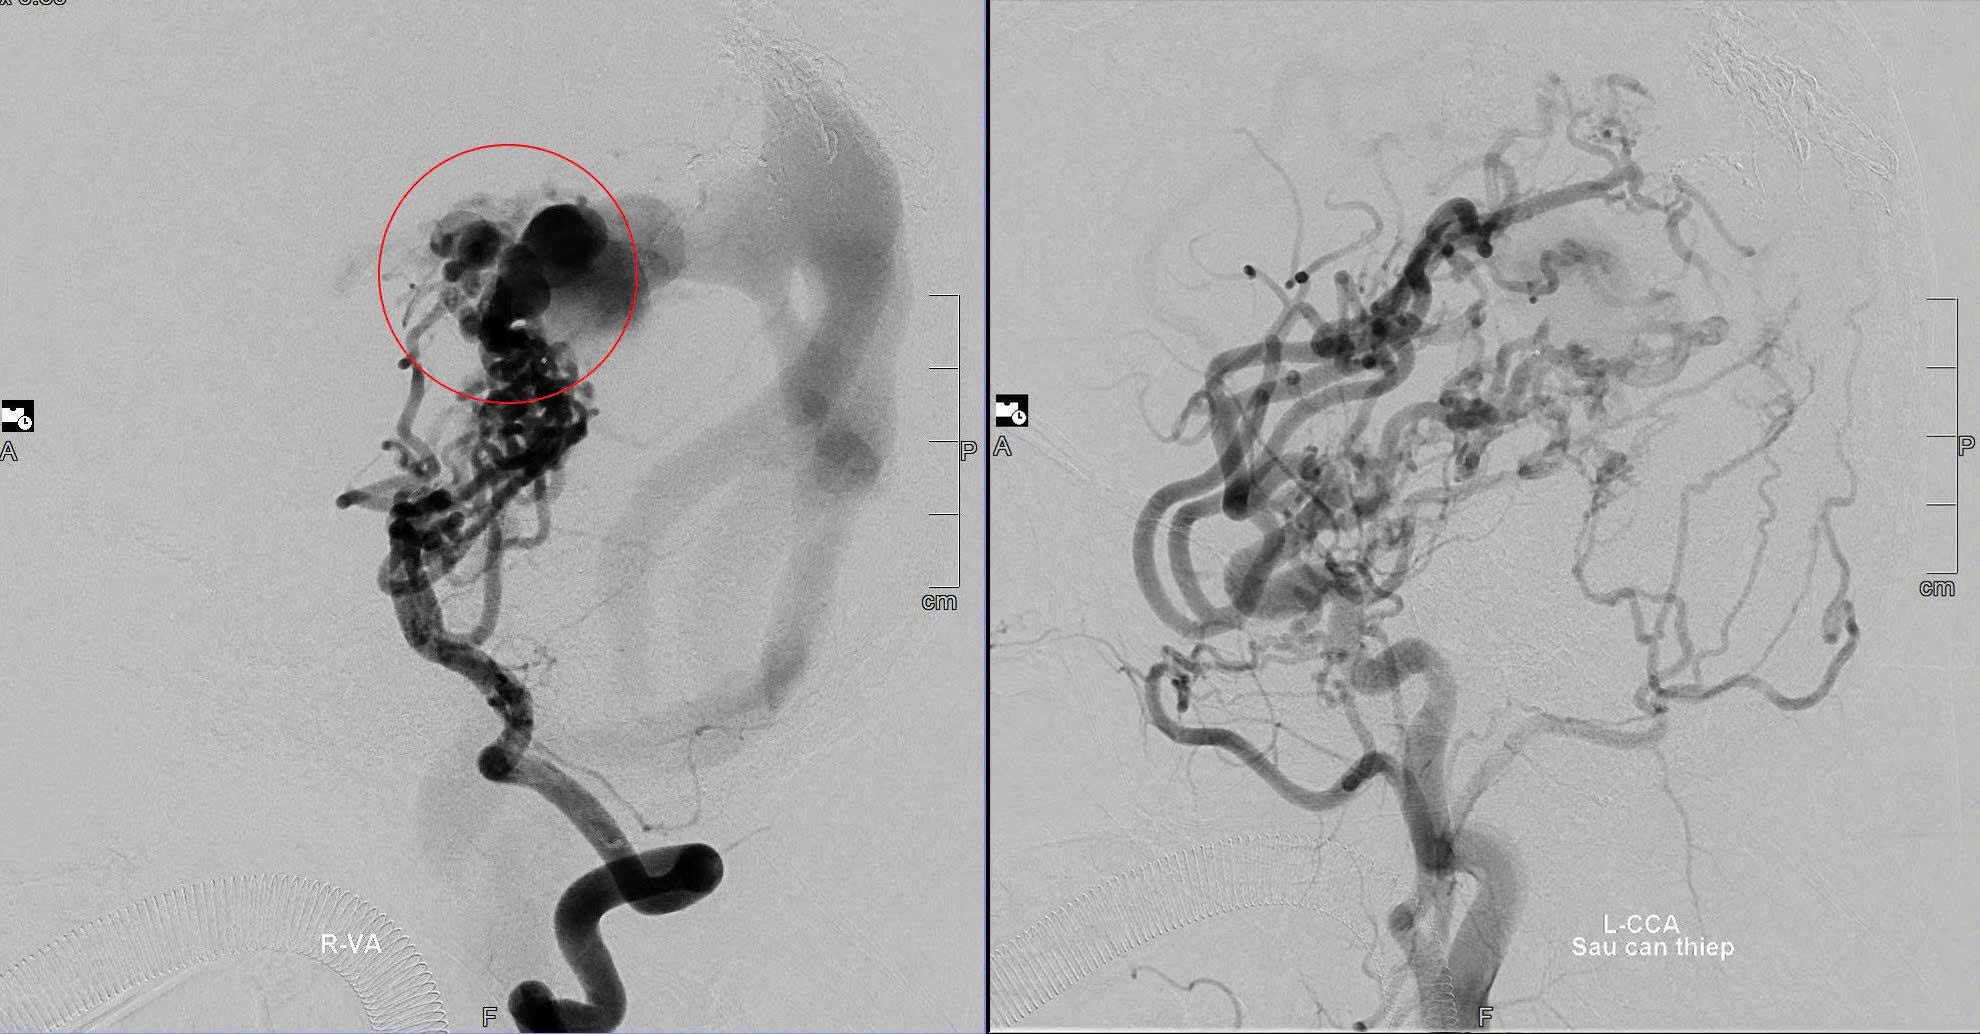

Chiến lược can thiệp được các bác sĩ hội chẩn là can thiệp nhiều lần cho bé để giảm nhẹ, giảm nguy cơ vỡ khối dị dạng. BS.CKI Dương Hoàng Linh, đơn vị can thiệp DSA, bệnh viện S.I.S Cần Thơ chia sẻ thêm: "Suốt 10 năm, bé D. đã trải qua 8 lần can thiệp mạch não. Mỗi lần là một cuộc chiến sinh tử, đòi hỏi bản lĩnh và sự tận tâm của đội ngũ y bác sĩ cùng niềm tin mãnh liệt từ gia đình."

Hình ảnh DSA mạch máu não trước và sau can thiệp